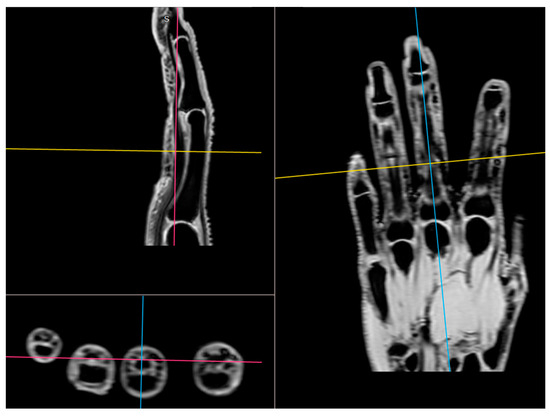

2.4. Magnetic Resonance Imaging

Cartilage Thickness and Distal Phalanx Length in MRI